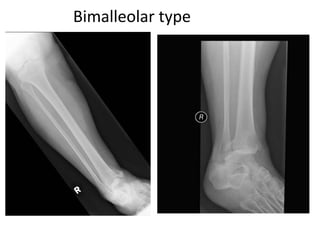

Bimalleolar fracture.pptx

BIMALLEOLAR FRACTURES mechanism and anapath.pptx

Presentation of bimalleolar fractures by site and fracture type ...